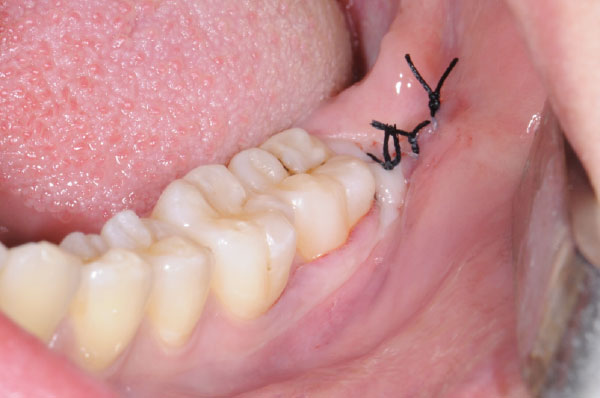

L'intervento segue precisi protocolli chirurgici. Dopo l'esecuzione di un'anestesia loco-regionale, si procede all'allestimento di un lembo di accesso mucoperiosteo a spessore totale, la cui scelta è determinata principalmente dalla profondità dell'inclusione e dalla posizione del terzo molare. In tutti i casi, il lembo deve creare un sufficiente accesso chirurgico (visivo e strumentale), evitare le strutture anatomiche circostanti (nervo linguale, arteria facciale), consentire un corretto riposizionamento del lembo e un'agevole sutura.

Il decorso postoperatorio che segue l'intervento chirurgico di avulsione può essere caratterizzato da diversi segni e sintomi, è importante informare il paziente sulla sintomatologia più frequente che comprende trisma, edema della zona interessata e sanguinamento.